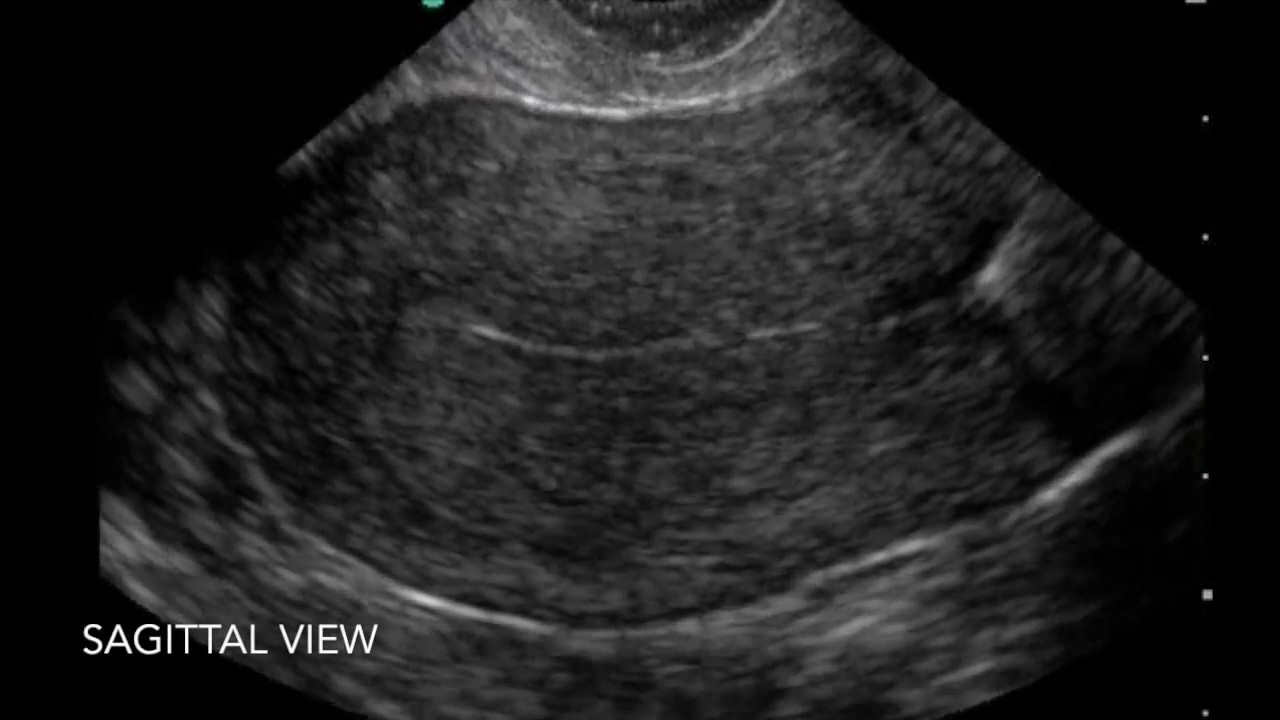

During an iud insertion, the pain happens in steps. According to familydoctor.org, an information website produced by the american academy of family physicians, lower abdominal pain is a common complaint among women with reproductive tract problems. Pain in the low back to a specific disease, rather it is a symptom from variety of diseases and problems.